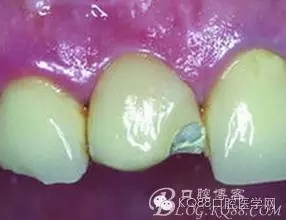

臨床沒有永遠的100%成功,每一點小的失誤都可能導(dǎo)致修復(fù)結(jié)果的失敗。臨床中烤瓷牙蹦瓷也是一種臨床常見現(xiàn)象。當(dāng)然如果嚴(yán)格按照技術(shù)要求和標(biāo)準(zhǔn)步驟去做,烤瓷牙蹦瓷的幾率并不高。但由于烤瓷牙制作過程步驟繁雜,每個細節(jié)都可能出現(xiàn)失誤,如金屬過融,噴砂機內(nèi)石英砂污染,反復(fù)上瓷修補增加進爐次數(shù)等,都可能導(dǎo)致增加蹦瓷風(fēng)險。而且患者在使用中也可能因咬到硬物等原因,造成蹦瓷的現(xiàn)象。

既然不可避免我們就要想辦法解決。遇到烤瓷牙蹦瓷首先我們要分析烤瓷牙蹦瓷的原因。如果是因為金屬支撐厚度不足,內(nèi)應(yīng)力過大等不良設(shè)計導(dǎo)致的蹦瓷我個人不建議修補。如果是瓷層厚度不足,我建議取冠從新預(yù)備牙齒再制作烤瓷牙。如果是咬合關(guān)系導(dǎo)致的我們要糾正咬合后再修復(fù),因意外咬硬物或外傷造成的蹦瓷我們都可以考慮用樹脂直接修復(fù)。經(jīng)常還會有人樹脂修復(fù)烤瓷牙大概能維持多久,其實這種問題我也很無奈,因為同樣是樹脂充填有的人做完可以維持五年以上的完美效果,而有些人做完幾個月就掉了。所以我一般都會說你樹脂充填能維持多久烤瓷牙蹦瓷修復(fù)就能維持多久。